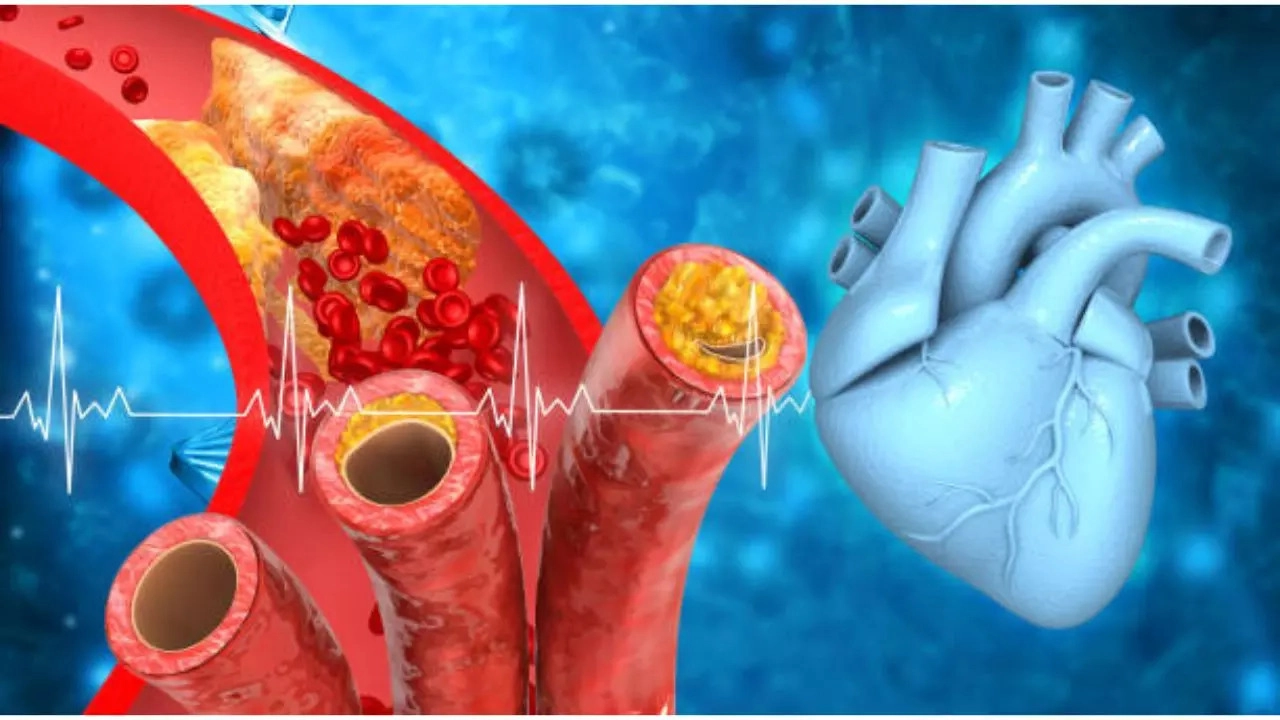

全身との深い関わり

口腔外科のもう一つの大きな特徴は、「全身疾患との関係性」です。

お口の中の炎症が心臓疾患に関与したり、糖尿病の方が抜歯をする際に特別な配慮が必要だったりと、お口のトラブルは体の他の部位と密接に繋がっています。

そのため、口腔外科医には、歯科の知識だけでなく、内科や外科を含む広範な医学的知識が求められます。